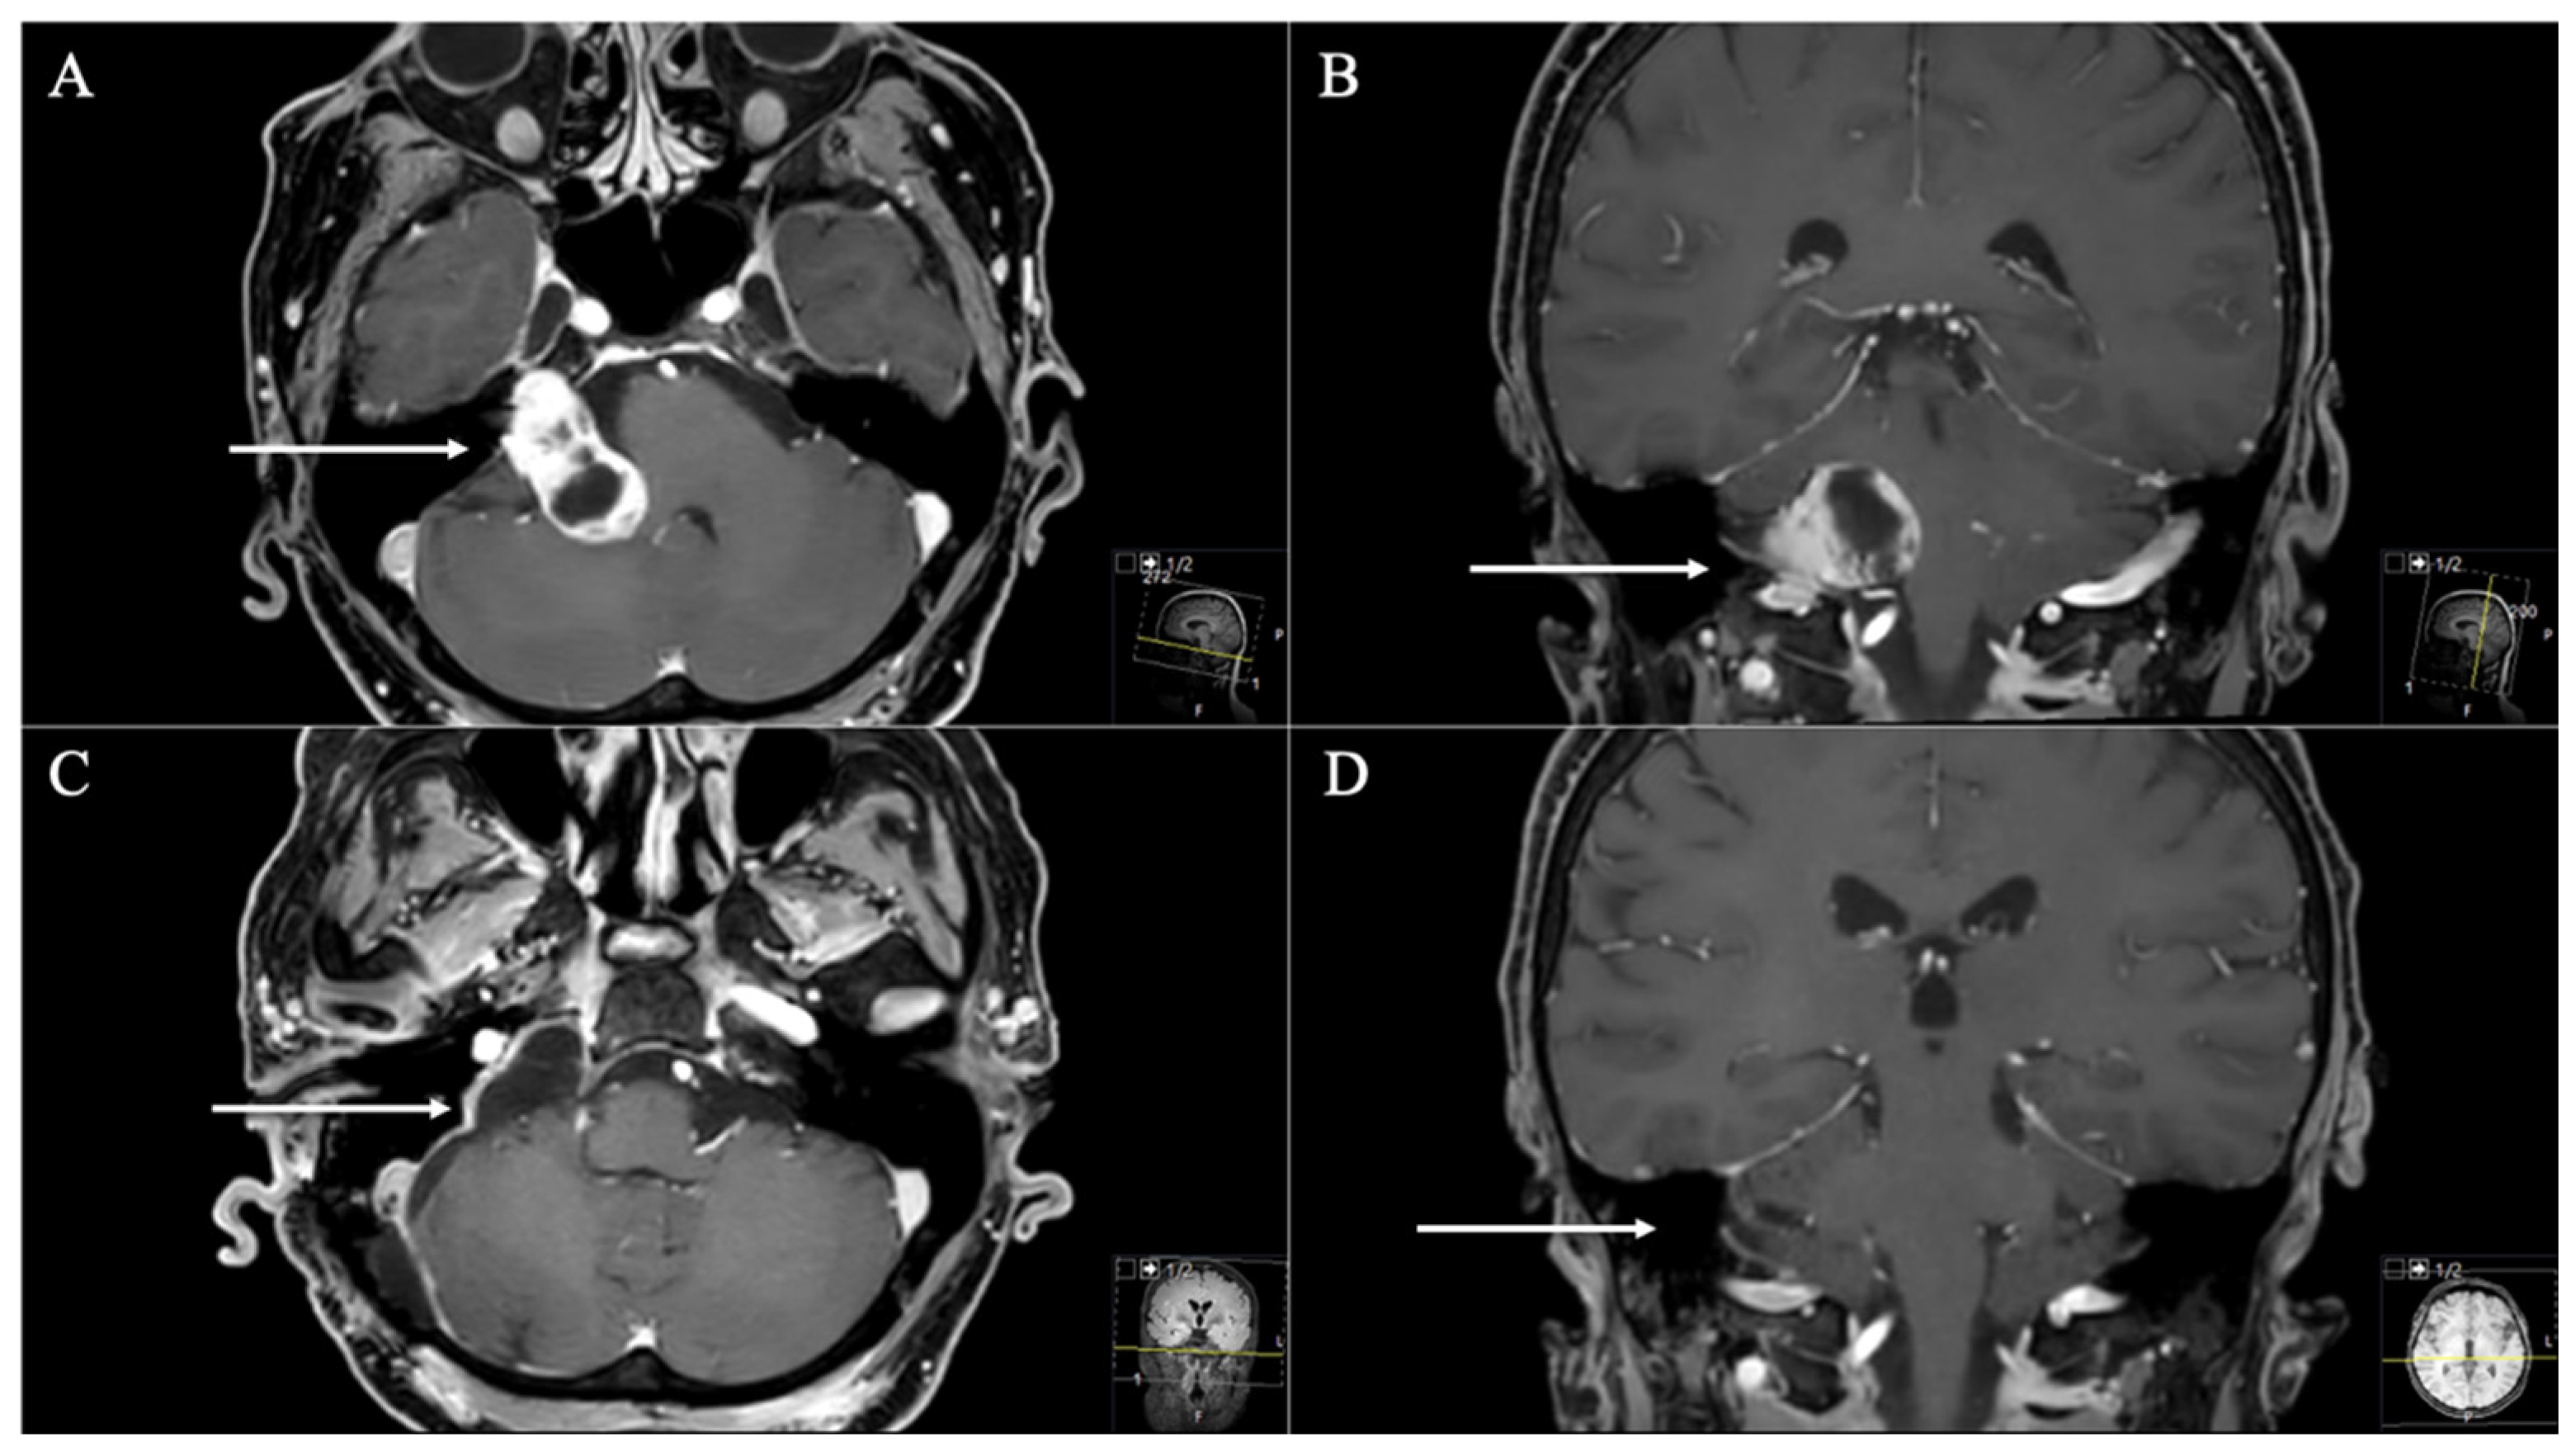

3. Results

3.1. Patient Population

3.2. Postoperative Outcome